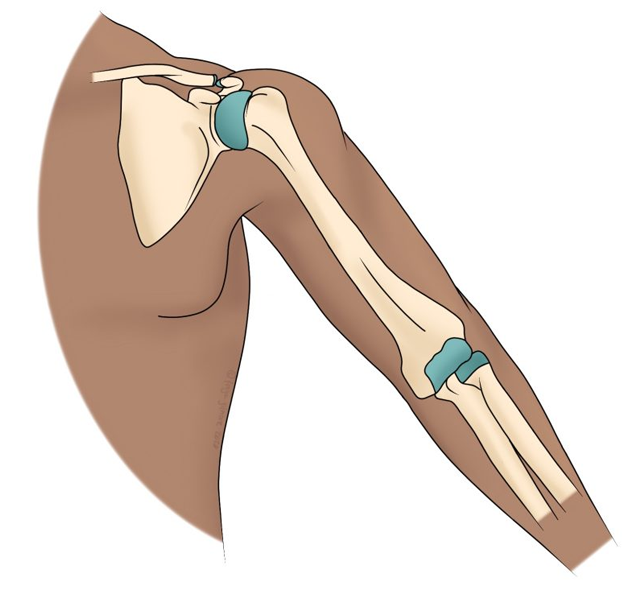

Types of Wrist Fractures

- Distal Radius Fracture (Colles or Smith fracture): The most frequent type, occurring near the wrist joint.

- Scaphoid Fracture: Involves one of the small carpal bones, often missed without proper imaging.

- Complex/Comminuted Fracture: Multiple bone fragments requiring specialized fixation techniques.

Surgical Techniques

Depending on the fracture type, our surgeons may perform:

- Open Reduction and Internal Fixation (ORIF): Using plates and screws to accurately realign the bone.

- External Fixation: A stabilizing frame outside the wrist for severe or open fractures.

- Percutaneous Pinning: A minimally invasive option using metal pins to secure the fracture.